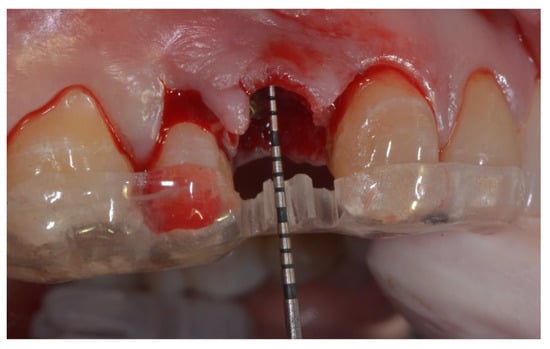

All patients rinsed for one minute with chlorhexidine mouthwash 0.2% before the surgery (and two times a day for the following three weeks). Under local anesthesia using lidocaine (adrenaline 1:50,000), patients were operated with the same surgical approach consisting of minimally invasive tooth extraction, without raising a muco-periosteal flap. Great attention was taken to reduce the damage to the vestibular bone plate and to maintain the integrity of the alveolar bone morphology. The extraction sockets were thoroughly debrided to remove all soft tissue, subsequently, the acrylic custom-made template was used to take the horizontal and vertical bone measurements. The surgical template was stabilized on the adjacent teeth to allow reproducible horizontal and vertical measurements at the different time points of the study. The vertical measurements were performed taking the surgical stent as reference point, as shown in Figure 1.

Figure 1. Fresh extraction socket: positioning of a custom acrylic template used to take the horizontal and vertical bone measurements during the surgery (T0).